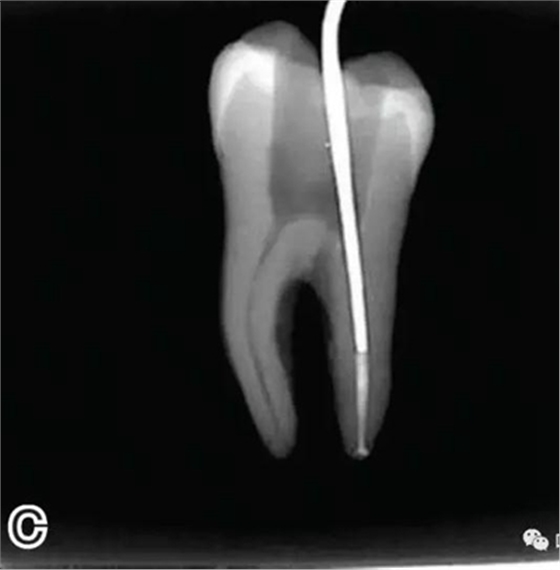

4、放置主尖及糊劑

將主尖的尖1/3 部分蘸一薄層根充糊劑,緩慢插入根管內(nèi),并左右旋轉(zhuǎn)主尖,以將根充糊劑均勻涂布于根管壁上,如圖4所示。

圖4 放置主尖及糊劑,A.放置主尖及糊劑 B.X線片下示主尖及糊劑的放置